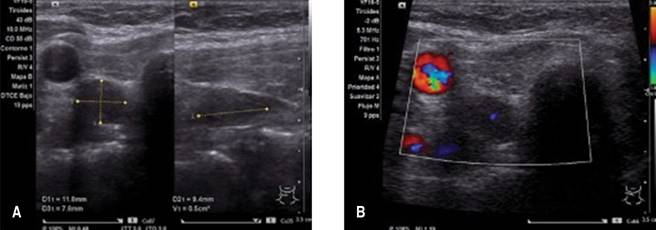

Mediante ultrasonido (USG) tiroideo se observó una imagen nodular hipoecogénica de 11.8 × 9.4 × 7.8 mm, volumen de 0.5 cm3, localizada posterior al lóbulo tiroideo derecho, con vascularidad interna, sugestiva de adenoma paratiroideo (Figura 1). Con esta información más los datos de laboratorio se llegó al diagnóstico de pancreatitis aguda grave secundaria a hipercalcemia por HPTP.

Se ha reportado en la literatura que hasta 80% de los casos el HPTP se origina por un adenoma paratiroideo.(10) El paciente que reportamos no presentaba a la palpación algún nódulo en la región tiroidea, por lo que se realizó búsqueda intencionada por ultrasonido, encontrándose el nódulo en el polo inferior del lóbulo derecho de la glándula paratiroides (Figura 1).